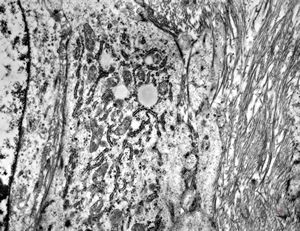

M,56y. | amyloidosis - tendon